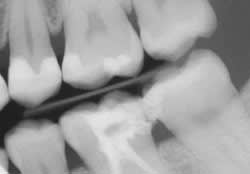

Venus Bulk is compatible with any methacrylate-based restorative material designed for Class I and Class II occlusal restorations, such as Venus Diamond (Heraeus Kulzer). Another quality of this material is its higher resistance to wear in contact areas, along with a superior compressive strength of 331 MPa and high flexural strength of 120 MPa (manufacturer’s data). Venus Bulk Fill is highly radiopaque, therefore restorations are easy to detect on dental radiographs (Figure 1).

A 42-year-old male was scheduled to have two Class II posterior direct composite restorations on teeth Nos. 18 and 19 after radiographs revealed caries under old restorations (Figure 2). A 1556 carbide bur was used to remove the old restoration and caries, as well as to prepare the cavity. When composite is the restorative material to be used, a traditional G.V. Black geometrical preparation is not necessary, because composite does not require minimum depth, minimum width, or mechanical retention like amalgam does. The key is to fully remove the caries in the most tooth-conserving fashion.